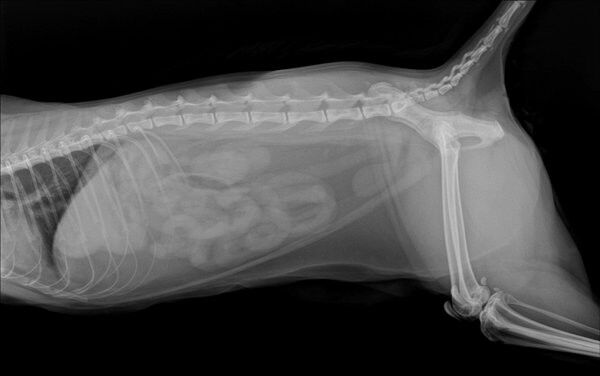

IBD는 증상만으로 확진이 어렵기 때문에, 분변검사, 혈액검사, 복부초음파, 필요시 내시경 조직검사 까지 단계적으로 진행합니다.